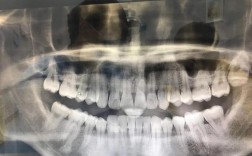

(1)口腔全景片(曲面断层片,Panoramic Radiography, PANO)

- 原理:通过X线球管和胶片同步旋转,一次性拍摄全口牙齿、牙槽骨、颌骨及周围结构的二维影像。

- 优势:视野广,可观察全口牙列、牙槽骨整体情况,操作简单、辐射剂量低(约0.007mSv,相当于1/10次胸片),价格便宜(约100-200元)。

- 局限性:二维成像,存在影像重叠(如上下牙槽骨重叠),无法精确测量骨厚度、密度,对细微骨缺损或神经管位置的判断准确性有限。

- 适用场景:初步筛查、简单牙列缺损(如单颗后牙缺失,骨量充足)、无复杂病史(如无上颌窦炎、无颌骨手术史)的患者。